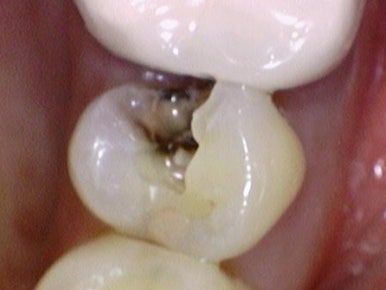

저희 연세 예 감 치과는 다수의 구강카메라를 보유하여

치료해야 하는 치아의 이유를 환자분께 빠르게 직접 보여드리고 기록합니다.

필요한 경우에는 치료 중간중간 바로바로 구강카메라로 찍어서

깊은 충치를 보여드립니다.

치료 전, 치료 중간 신경치료해야 할 만큼 깊은 충치를 보여드리기 위해 찍은 사진